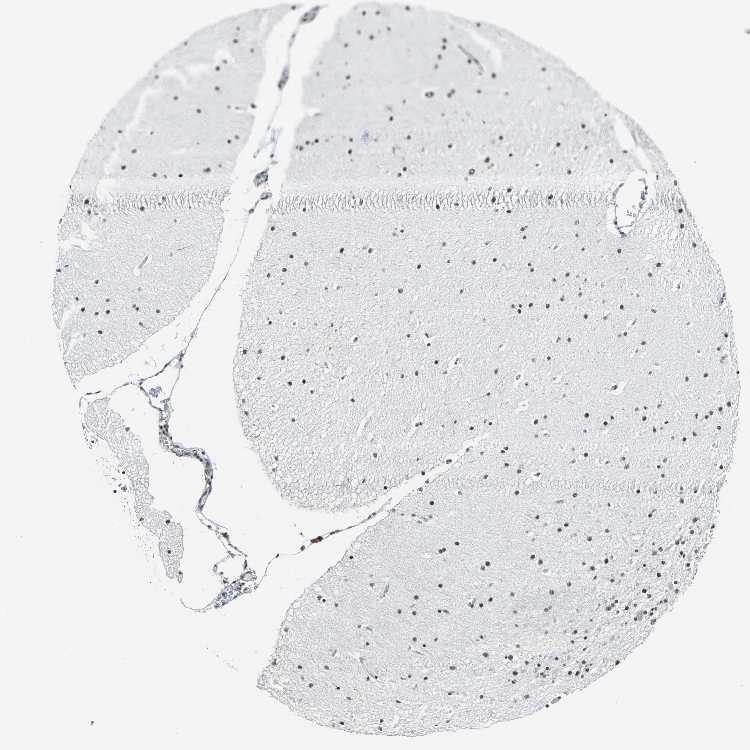

BRAIN CEREBELLUM Show tissue menu

CEREBELLUM - Expression summary

CEREBELLUM - Antibody stainingi

Antibody staining in the annotated cell types in the current human tissue is reported as not detected, low, medium, or high, based on conventional immunohistochemistry profiling in selected tissues. This score is based on the combination of the staining intensity and fraction of stained cells.

Each image is clickable and will lead to virtual microscopy that enables deeper exploration of all samples and also displays staining intensity scores, fraction scores and subcellular localization as well as patient and tissue information for each sample.

Antibody HPA006628

Purkinje cells High

Cells in granular layer High

Cells in molecular layer High